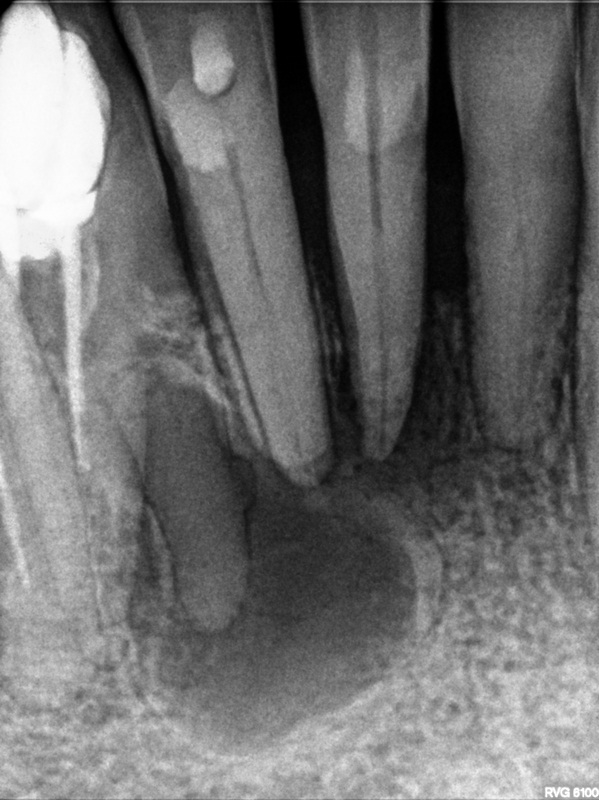

Bogata w płytki i leukocyty fibryna jest stosowana w regeneracji tkanek od ponad 15 lat. Pozytywny wpływ PRF (platelet-rich fibrin) na regenerację tkanek miękkich jest niewątpliwy, bezsporny i częściowo udowodniony w badaniach klinicznych i analizach biochemicznych. Wpływ PRF na regenerację tkanki kostnej jest obserwowany klinicznie, ale nadal niedostatecznie poznany jest mechanizm tego zjawiska.

Platelet- and leukocyte-rich-fibrin has been used in regeneration of tissue for more than 15 years. The positive influence of PRF on the regeneration of soft tissue is undoubtedly, without question and partially proven in clinical studies and biochemical analysis. Influence of PRF on regeneration of bone tissue is observed clinically but the mechanism of this phenomenon is still not sufficiently known.